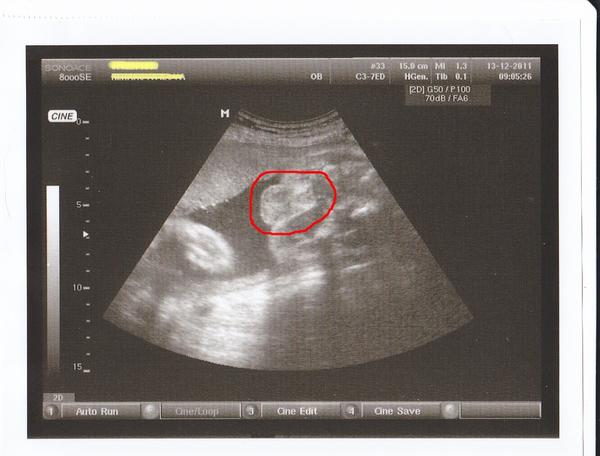

vypadá to opravdu na holčičku, je to pohled jakoby zezdola mezi roztažené nožičky.Ty dvě velké bílé kuličky jsou hlavice stehenních kostí kolem jsou stehýnka a mezi nima vidím holku 🙂

Podle mě je to brané ze špatného úhlu a těžko pak říct, počkala bych do další kontroly a tak by už to mělo být vidět zřetelněji, ale z mého pohledu to vypadá jako kulky a pindík, takže za mě taky kluk. Ale nevěsila bych hlavu, jisté to bude po porodu, mám pár kamarádek, kterým se dr. zaručoval že to bude kluk a bylo tomu naopak.

já tam teda (na té spodní fotce) vidím kávové zrníčko a tudíž holčičku. Chlapeček už by měl podstatně zřetelně vyrýsovaný pindík. Moje holčička (3x potvrzená-ve 13.tt, v 17.tt a ve 20.tt, tak snad skutečná 🙂 ) vypadá na uzv podobně, když jsem čekala dle uzv chlapečka (který se taky narodil), tak ten pindík je opravdu už hezky vidět a to už někdy v 17.tt, natož ve 22.tt. Tady ho teda hledám marně a hlavně-věřila bych doktorovi a ne laikům na MK 😉 .